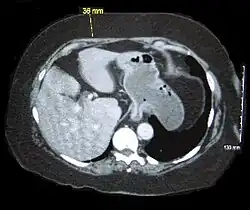

| Abdominal computed tomography of an obese person showing excess abdominal adiposity | |